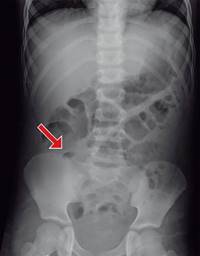

Masculino de nueve años con antecedente de haber sido intervenido quirúrgicamente por apendicitis aguda dos años y medio previos a su padecimiento actual, el cual inicia 10 días antes de su ingreso y se caracteriza por dolor abdominal generalizado y vómitos en dos ocasiones de características gastroalimentarias, manejado por facultativo con analgésicos no especificados y sin mejoría. Continúa con dolor abdominal de predominio en el cuadrante inferior derecho acompañado de náuseas y vómitos. Motivo por el cual acude al Servicio de Urgencias del hospital, en donde se encuentra al paciente con dolor en cuadrante inferior derecho, posición en gatillo y con datos de irritación peritoneal. Se solicitan laboratoriales, reportándose hemoglobina de 13.0 mg/dl, hematocrito de 38.2%, 15.15 × 109, 76.4% neutrófilos. La placa simple de abdomen muestra una imagen de asa fija en fosa iliaca derecha (Figura 1). Se solicita ultrasonido abdominal, el cual reporta una colección de 5 × 4 cm (Figura 2), por lo que se interconsulta al Servicio de Cirugía General ya que no se contaba con cirujano pediatra en el turno; 24 horas después de su ingreso es valorado por cirugía, encontrando al paciente con discreta resistencia voluntaria en cuadrante inferior derecho e irritación peritoneal. Se solicita una resonancia magnética abdominal, para determinar la probable etiología de la colección, la cual reporta una colección amorfa en fosa iliaca derecha, de bordes irregulares y bien definidos, con medidas de 5.1 × 4.3 × 4.9 cm en sus diámetros longitudinal y anteroposterior transverso, respectivamente, compatibles con absceso en fosa iliaca derecha.

Figura 1: Placa simple de abdomen en la que se aprecia una rectificación antálgica de la columna. La flecha indica un asa fija en fosa iliaca derecha.